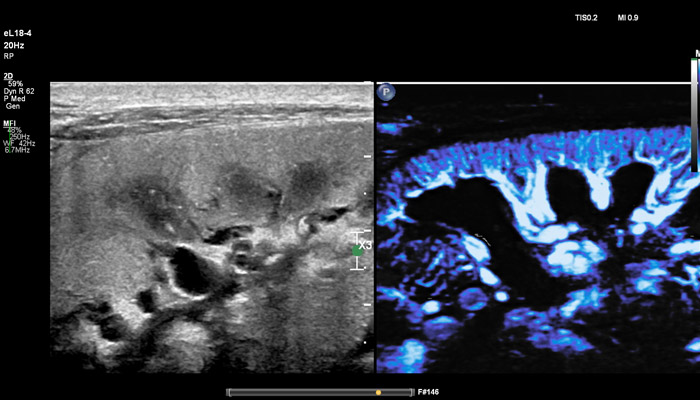

Рак молочной железы является вторым по распространённости онкологическим заболеванием в мире и составляет около 25% случаев заболеваний среди женщин. Сегодня многие врачи полагаются на ультразвуковую диагностику в выявлении рака у пациенток с уплотнениями ткани молочных желез. При маммографии плотные ткани могут маскировать небольшие раковые поражения. Комплексное исследование молочных желез с применением ультразвукового метода может привести к выявлению еще трех-четырех случаев онкологических заболеваний на 1 тысячу женщин. В распоряжение клиницистов должны попадать решения, которые не только улучшают выявление новообразований и повышают точность диагностики, но также увеличивают пропускную способность кабинета и производительность при сохранении высокого уровня доверия. Линейный матричный датчик eL18-4 используется клиницистами Европы как современное решение для визуализации молочных желез, которое повышает надежность диагностики с помощью таких мощных инструментов, как превосходная визуализация в B-режиме, компрессионная эластография, эластография сдвиговой волной и высокочувствительная визуализация кровотока (MicroFlow Imaging). Кроме того, панорамный режим полезен для оценки распространенности заболевания, выявления большого количества фиброзных изменений и определения расстояния между двумя очагами. Всякий раз, при исследовании молочной железы, превосходное качество изображения и эластография необходимы, чтобы поставить точный диагноз с первого раза и помочь в лечении пациентов.

Накопленный за последние 15 лет клинический опыт показывает, что применение эластографии в дополнение к каждому ультразвуковому обследованию молочной железы приводит к сокращению количества проводимых биопсий, которые раньше проводились в более 80% случаев, но впоследствии оказывались ненужной процедурой".

Ричард Г. Барр, MD, PhD

Северо-Восточный Медицинский Университет Огайо, Огайо, США

Линейный матричный датчик eL18-4 поддерживает режим высокочувствительной визуализации кровотока (Philips MicroFlow Imaging), новый запатентованный метод, который обеспечивает инновационный подход к оценке сосудистого русла. Визуализация MicroFlow преодолевает многие барьеры, связанные с традиционными методами обнаружения кровотока в малых сосудах, обеспечивая высокое разрешение при минимальных артефактах. Метод MicroFlow Imaging поддерживает высокую частоту кадров и качество изображения, применяет инновационные методы сокращения артефактов. Варианты вычитания 2D-изображений, смешивания и параллельного отображения обеспечивают превосходную визуализацию в различных клинических случаях.